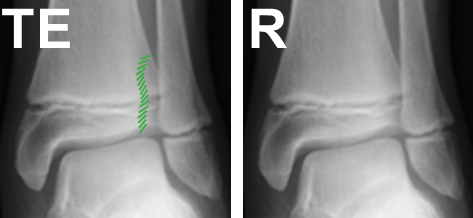

Growth plate injuries

In children, the weakest point around a joint is the growth plate. In adults, it is usually the ligaments of the joint. Growth plate fractures occur in typical patterns and are described using the Salter-Harris classification. The word SALTER (I – Straight across, II – Above, III – Lower, IV – Trough Everything and V – cRush) is a useful acronym to remember this classification.

- Type II fractures are by far the most common

- Type III and IV are intra-articular fractures and require anatomical reduction.

- Type V is associated with a high rate of growth disturbance.